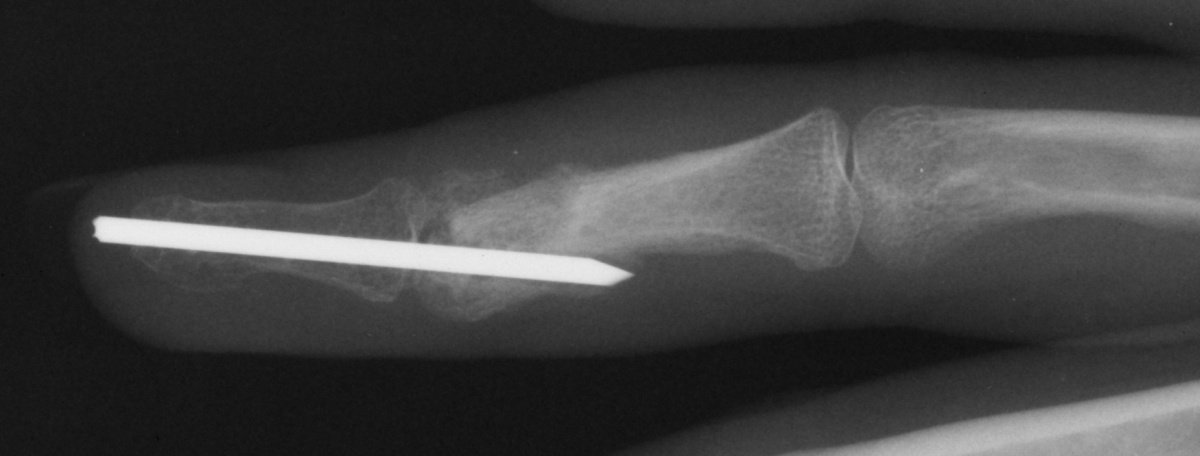

| Case 1. This 18 year old man

presented with a two year history of pain and swelling of the distal

aspect of his proximal phalanx. |

| Plain films showed

sclerosis within a radiolucent area and adjacent cortical/endosteal

sclerosis. |